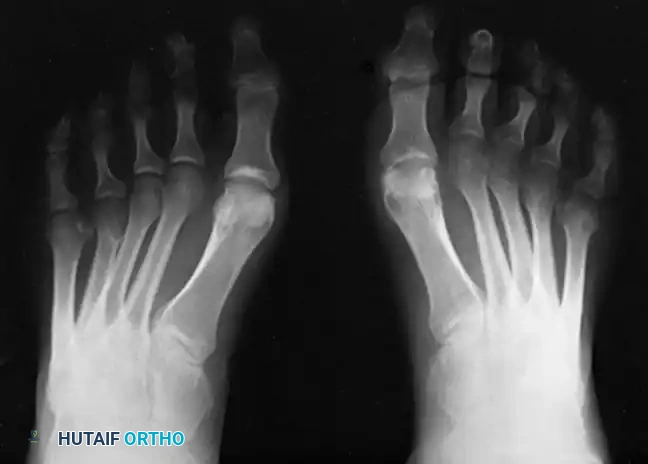

Radiographic Evaluation

Brockway’s 1940 axiom remains true: "Cavus feet should never be operated upon until radiographs with the patient standing have been taken."

Standard weight-bearing anteroposterior (AP) and lateral radiographs of the foot, along with a weight-bearing AP of the ankle, are required.

Key Radiographic Parameters:

* Meary’s Angle (Talus-First Metatarsal Angle): Normally 0 degrees. In a cavus foot, the angle is convex upward (apex dorsal), indicating midfoot/forefoot equinus.

* Calcaneal Pitch: Normally 15 to 20 degrees. In a cavus foot, it is significantly increased (>30 degrees).

* Hibbs Angle: The angle between the longitudinal axis of the calcaneus and the first metatarsal. It approaches 90 degrees in severe cavus (normal is ~140 degrees).

* Talonavicular Coverage: Assessed on the AP view to quantify midfoot adduction.

Fig. 7: Standing lateral radiograph demonstrating an increased calcaneal pitch and a severe apex-dorsal Meary's angle.